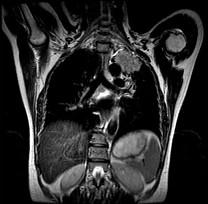

问题 男,68岁,声音嘶哑半个月,行MRI检查如图,其最可能的诊断为 ( )

选项 A.右上肺癌 B.左上肺结核球 C.左上肺炎性假瘤 D.左上肺癌 E.左上肺动静脉瘤

答案 D